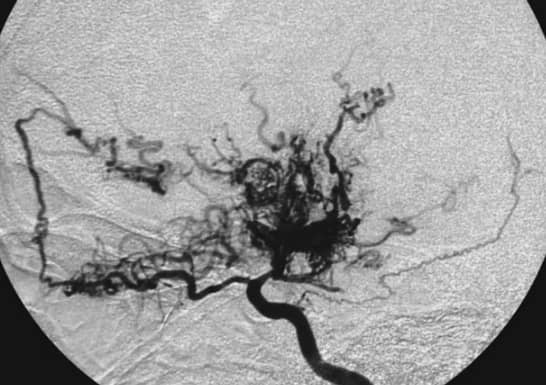

모야모야병은 뇌의 주요 혈관들이 점차 좁아지는 질병입니다. 이로 인해, 뇌에 필요한 혈액 공급이 제대로 이루어지지 않게 됩니다. 이런 현상을 보완하기 위해 뇌 내의 작은 혈관들이 활성화되어 더 많이 형성됩니다.

이 작은 혈관들의 형태가 연기처럼 흐르는 모양을 닮아 '모야모야'라는 이름이 붙여진 것입니다. 이 이름은 일본어에서 유래하였으며 연기가 구름처럼 피어오르는 모양을 뜻하는 말에서 비롯되었습니다.

모야모야병은 뇌혈관조영술로 진단되며, 자세한 뇌혈류 검사 결과에 따라 치료가 진행됩니다.

직접 재관류 수술 두피의 두피 시간 동맥과 중간 뇌동맥을 직접 연결하는 방식입니다. 수술 후 바로 혈류가 증가하는 장점이 있으나, 어린아이들에게는 혈관이 얇아 기술적인 어려움이 있을 수 있습니다.

간접 재관류 수술

뇌의 경막, 시간 근육, 중간 수막 동맥, 털의 건대 등과 같은 혈관이 풍부한 표면 조직을 뇌 표면과 접촉시켜 새로운 혈관이 뇌로 자라게 하는 방식입니다.